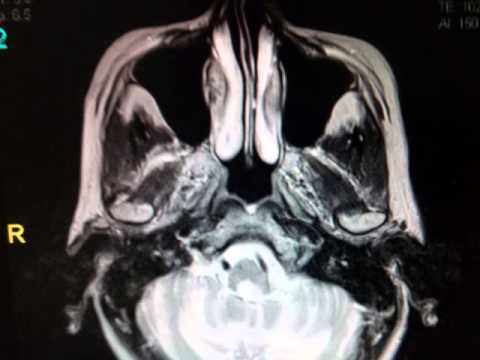

Untreated, hydrocephalus can result in brain damage or death. Ct/mri criteria for acute hydrocephalus include the following: Mri images are clearer and more precise than other forms of diagnostic imaging.

Ct scan of a brain. Medical imaging scans, either computer tomography (ct) or magnetic resonance imaging (mri), are used to diagnose hydrocephalus in adults and children. This diagnostic procedure uses a combination of large magnets, radio frequencies, and a computer to produce detailed images of organs and structures within the body. Soft tissues refer to muscles, fat, blood vessels.